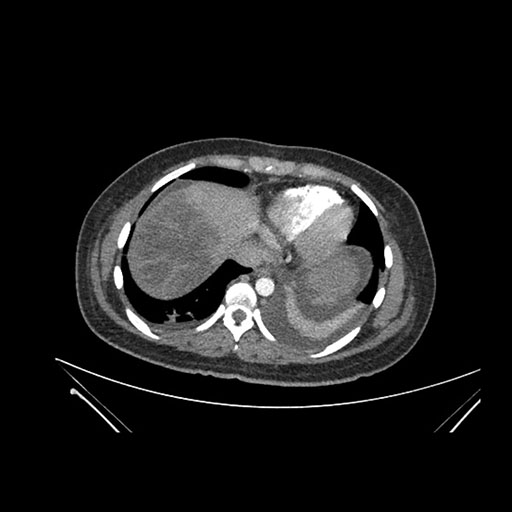

Imaging Analysis

Look through the patient's CT scan to identify any areas of concern for the necessary procedure.

Axial Arterial

Axial Venous

Based on initial findings, which issue(s) would you be most concerned about?